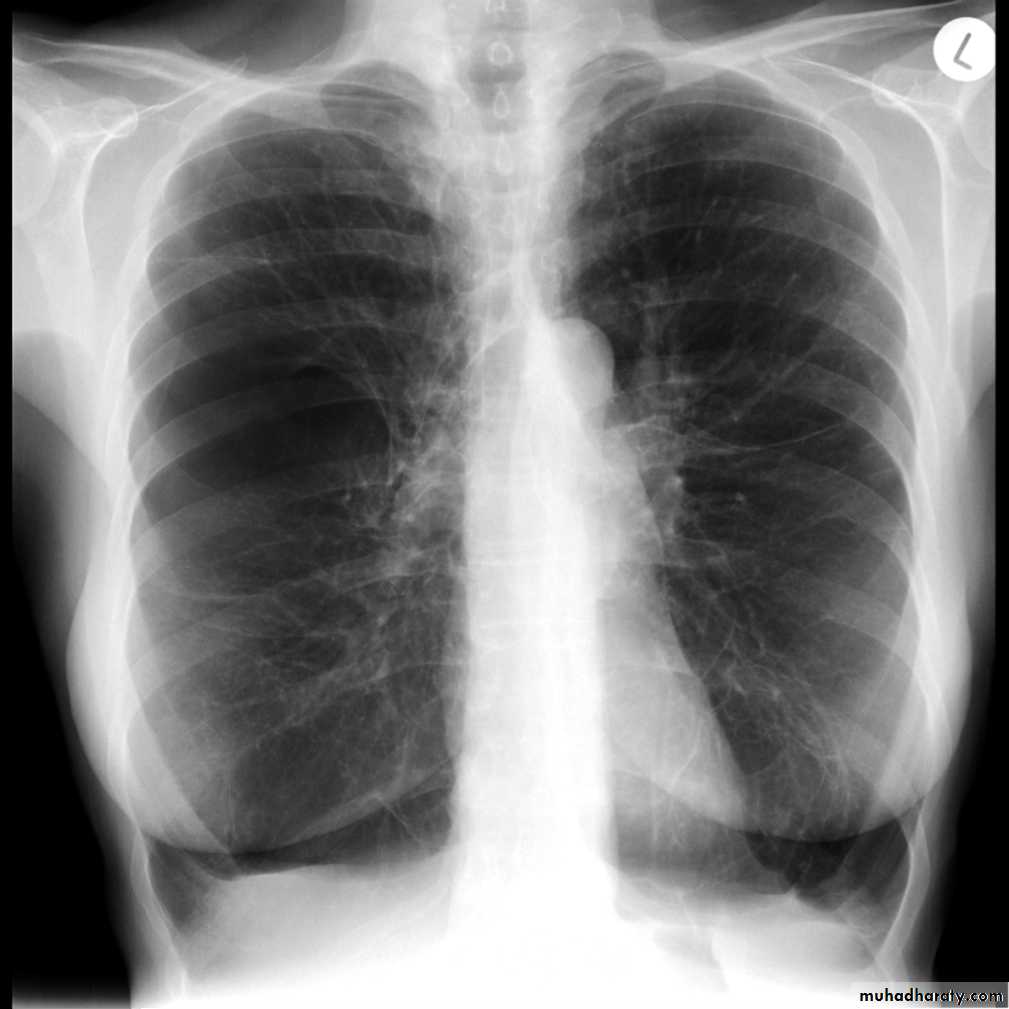

Plain filmExcept in the case of very advanced disease with bulla formation, chest radiography does not image emphysema directly, but rather infers the diagnosis due to associated features :

hyperinflation:

1.flattened hemidiaphragm(s): most reliable sign

2.ncreased and usually irregular radiolucency of the lungs

5.widely spaced ribs

9.vascular changes paucity of blood vessels ( absent pulmonary markings in outer 1/3 of the lung fields )